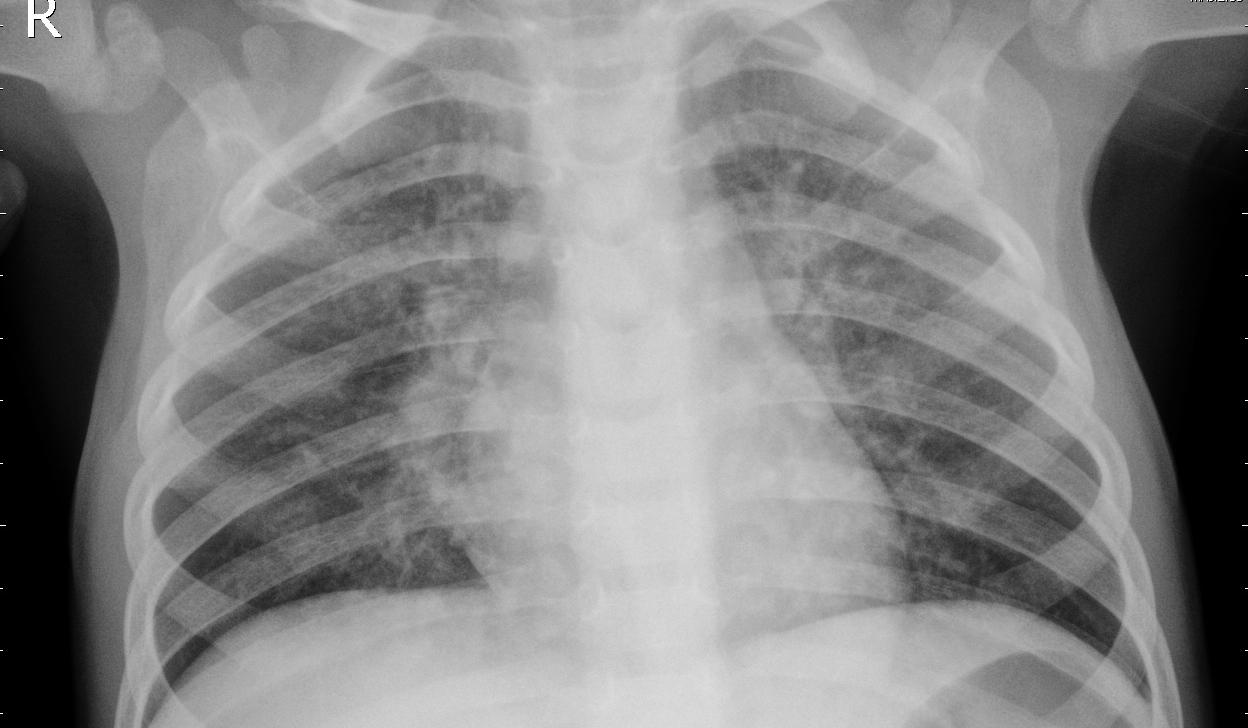

[Uncaptioned image] User: Given a chest X-ray image, determine whether the patient has a normal chest or pneumonia. Only output ‘normal’ or ‘pneumonia’.

LLaVA-Med-v1.5: ONLY ANSWER: The chest x-ray image shows a normal chest.

Ours: Pneumonia.

Ground truth: Pneumonia.